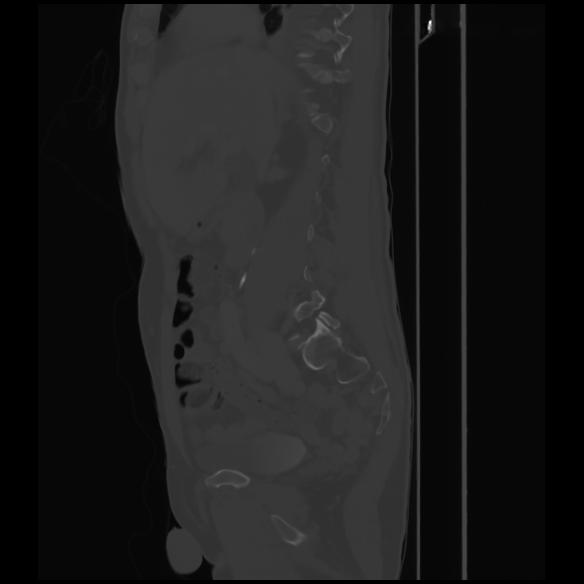

7 CUERPO,CE,Sagittal,3.000,CUERPO,Sagittal,